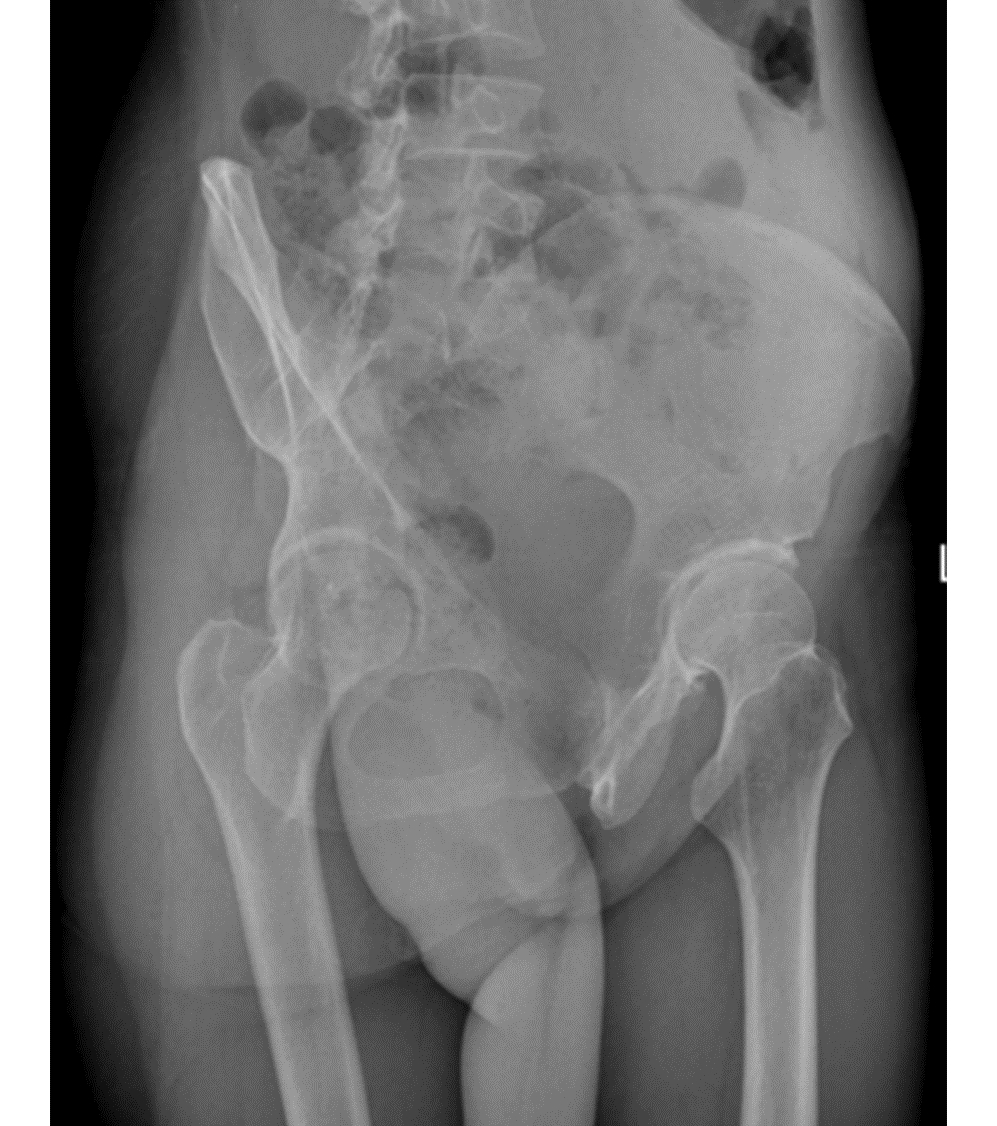

Analysis of Wilson's disease presented with osteoarticular symptoms in 14 patients

Chengwei KANG, Hongyun WO, Changchao DONG, Zhaokui YAN, Xiaobing PU

2022, 38(12): 2814-2817. DOI: 10.3969/j.issn.1001-5256.2022.12.023

Abstract(2049) HTML (1211) PDF (2195KB)(84)

Abstract: